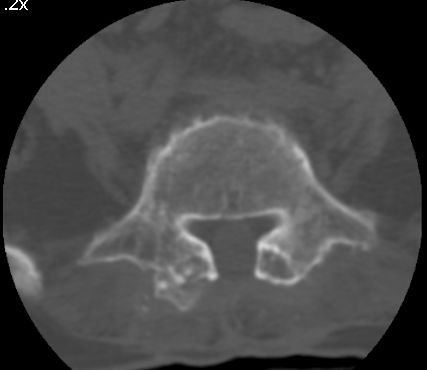

以下是引用余辉在2007-9-4 21:00:00的发言:[br]椎体棘突有点异常(像是被切割了),不知有否手术史,如椎体融合术等。单纯的退行性变可以出现椎间隙变窄,但同时一般会出现椎体上下缘的硬化增生,且椎体间完全融合的机率更小,本例椎体完全融合且椎体上下皮质缘破坏掉了,如果没有手术史,就应该考虑椎间盘炎性病变了,且椎体棘突及棘间韧带的变化也并不是不支持这个,多数小关节也融合了,且其形态也容易让人联想到如强脊炎及类风关等病变。[br][br][本贴已被 余辉 于 2007-9-4 21:03:55 修改过]

以下是引用chry3在2007-9-4 20:42:00的发言:[br]椎间盘病史?是什么样的病史,无双下肢放射痛,那就不是椎间盘突出了。是感染、什么性质的?[br]从图象看椎间隙消失,椎间盘组织未见,锥体滑脱是因为椎间盘溶解造成的[br]l4、5椎体骨质结构未见异常,l5上缘是l4的长期压迫所致[br]还是考虑椎间盘感染,结核。[br]